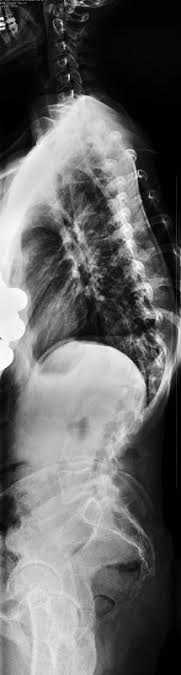

So today instead of posting about my love for Lululemon Striped Wunder Unders, I am posting some x-ray pictures, that I am sure you have all been dying to see. I waited impatiently for this CD to show up in the mail so I could finally post them and although it wasn’t a new pair of J brand jeans or an amazing spring blouse, I was still super excited to finally get it in the mailbox. Weird, right? Of course, once I actually look at them, its depressing and horrible. Not only does my spine curve side to side in an S, but it also curves front to back which is what causes my hump and is called Kyphosis. What you can’t see in these pictures is how my spine twists and rotates as well. And if you look really close, you can see my ribs basically rests on my hip bone. Sounds cool, huh?